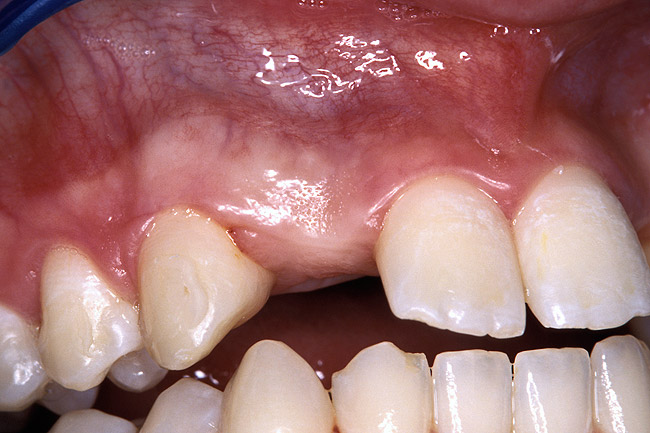

Periapical radiographs were taken to help determine the mesial-distal inclinations of the adjacent tooth roots (Figure 1). The radiographs revealed a serious issue, convergent roots for the right canine and right central, which eliminated that area as a potential implant-receptor site. The space between the left central and canine teeth was minimal, although the roots were relatively parallel. Clinical examination (manual palpation of the root eminences superiorly to the vestibule on the right side) confirmed the root convergence (Figure 2A). The flat, wide zone of the keratinized tissue and lack of interdental papilla was evident for the missing right lateral incisor. There was a marked difference in clinical appearance for the left lateral, which could impact the eventual plan of treatment (Figure 2B). Other significant clinical findings included bilateral facial bone concavities, which existed as a result of the congenitally missing tooth roots. As a diagnostic cue to the underlying bone topography, it is important to follow the demarcation between attached and unattached gingival tissue, and note the crestal width of the available keratinized tissue (Figure 2C).

Figure 2b  Pretreatment buccal views showed (A) root convergence, (B) a difference in clinical appearance of the left lateral, and (C) significant crestal width of keratinized tissue.

Figure 2b

Figure 2c  Pretreatment buccal views showed (A) root convergence, (B) a difference in clinical appearance of the left lateral, and (C) significant crestal width of keratinized tissue.

Figure 2c